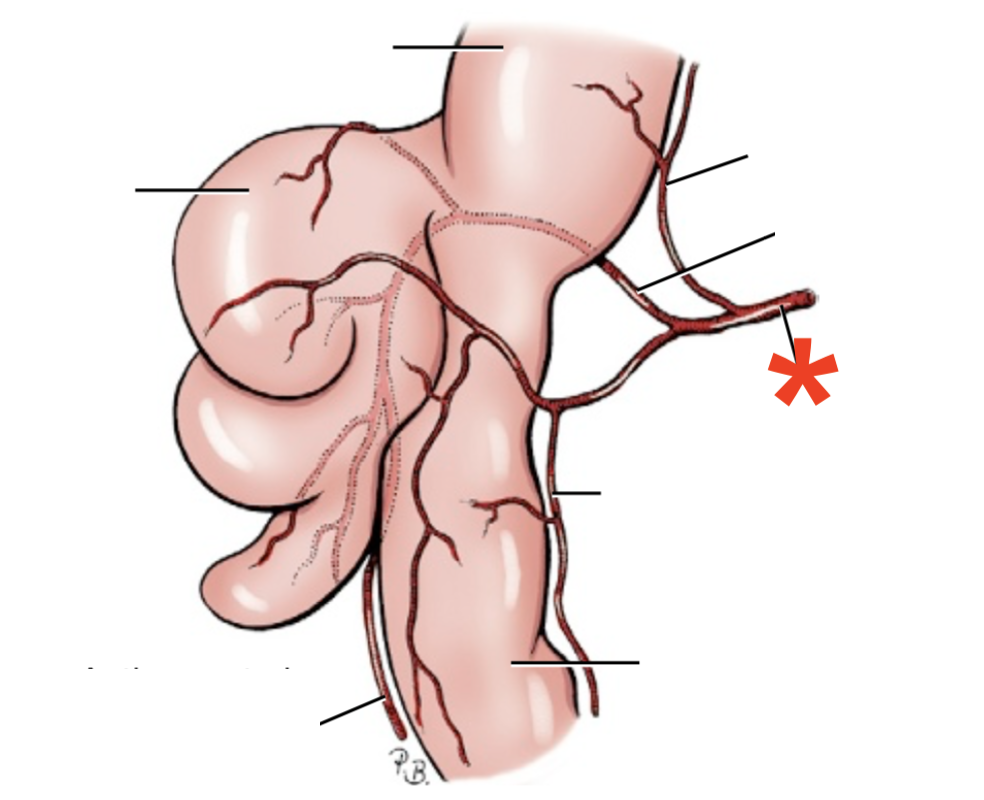

Q

A

A. coeliaca

- Supplies:

- Liver

- Spleen

- Pancreas

- Cranial duodenum

List the branching of *a. lienalis*

* Rr. lienales

* A. gastroepiploica sinistra

List the branching of *a. hepatica*

* *A. gastrica dextra*

* *A. gastroduodenalis*

* *A. pancreaticoduodenalis cranialis*

* *A. gastroepiploica dextra*

List the branching of *a.* *gastrica* *sinistra*

* *R. oesophagus*

* *Rr.* *gastrici*